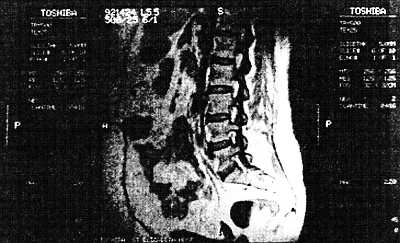

Магнитно-резонансное изображение способно показывать различия в мягких тканях лучше, чем получаемые компьютерным аксиальным томографом с помощью рентгеновских лучей, и может показать сечение пациента по любой из трех осей. На рис. 10.27 показано магнитно-резонансное изображение живота сбоку. Обратите внимание налетали позвоночника и хрящевые диски между позвонками, а также различные органы живота. Оборудование ЯМР особенно чувствительно при изображении мягких тканей, в то время как компьютерный аксиальный томограф хорошо отображает костные структуры.

Рис. 10.27. Магнитно-резонансное изображение области нижней части спины и близлежащих органов